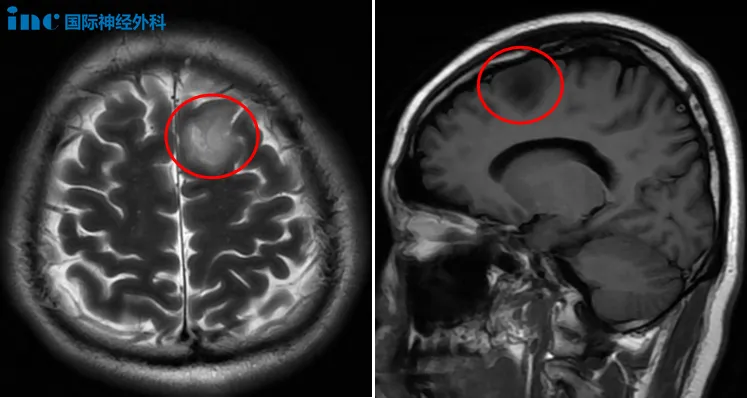

申先生刚步入而立之年,拥有幸福的家庭生活,但这一切几乎被一次偶然发现所影响。常规体检中,他被告知存在"颅内占位性病变"。尽管自觉身体健康,没有任何不适症状,为明确诊断,他与妻子一同前往医院进行详细检查。头颅核磁共振显示左侧额叶存在大小约27×23mm的病灶,考虑为低级别胶质瘤。